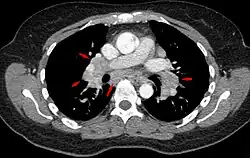

-

Hilar adenopathy especially on the person's left (AP CXR)

Hilar adenopathy especially on the person's left (lateral CXR)

Hilar adenopathy especially on the person's left (coronal CT)

Hilar adenopathy especially on the person's left (transverse CT)

Chest radiograph changes are divided into four stages:[104]

- bihilar lymphadenopathy

- bihilar lymphadenopathy and reticulonodular infiltrates

- bilateral pulmonary infiltrates

- fibrocystic sarcoidosis typically with upward hilar retraction, cystic and bullous changes

Although people with stage 1 radiographs tend to have the acute or subacute, reversible form of the disease, those with stages 2 and 3 often have the chronic, progressive disease; these patterns do not represent consecutive "stages" of sarcoidosis. Thus, except for epidemiologic purposes, this categorization is mostly of historic interest.[28]